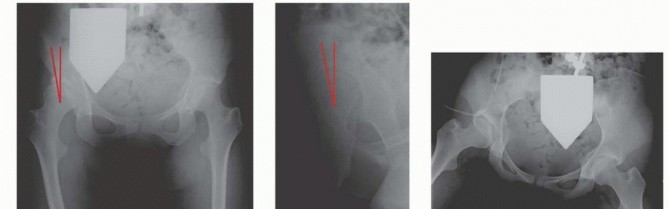

Innominate Osteotomy of Salter DEFINITION The Salter innominate osteotomy is commonly performed in conjunctio…